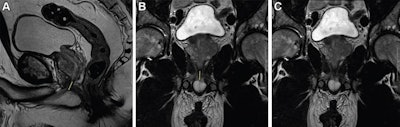

Preoperative MRI-based anatomic measures were obtained by four abdominal radiologists. The membranous urethra length was measured in the coronal and sagittal planes and defined as the distance from the prostate apex to the urethral entry into the penile bulb.